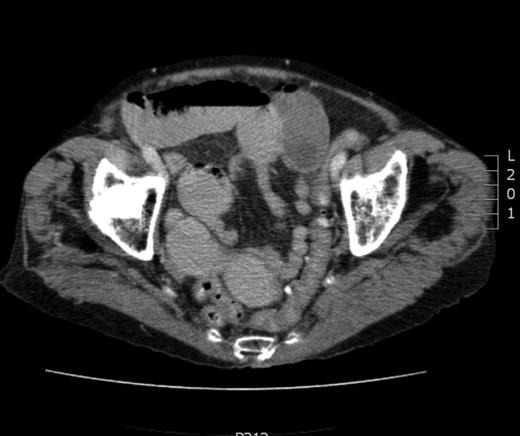

On examination, her vitals were stable. She displayed mild upper abdominal tenderness without signs of peritonism. Bowel sounds were present. Her haematological investigations were unremarkable. A plain film of abdomen was unremarkable. She was treated presumptively as a small bowel obstruction and non-operative measures were employed and the patient proceeded to have a computed tomography (CT) scan of the abdomen and pelvis, which indicated proximal small bowel obstruction secondary to a left obturator hernia (Fig. 1). She proceeded to emergent laparoscopy and subsequent mesh repair of left obturator hernia, containing an obstructed loop of small bowel. There was a concomitant femoral hernia that was repaired separately.

CT image. Proximal small bowel obstruction secondary to a left obturator hernia within white outline.